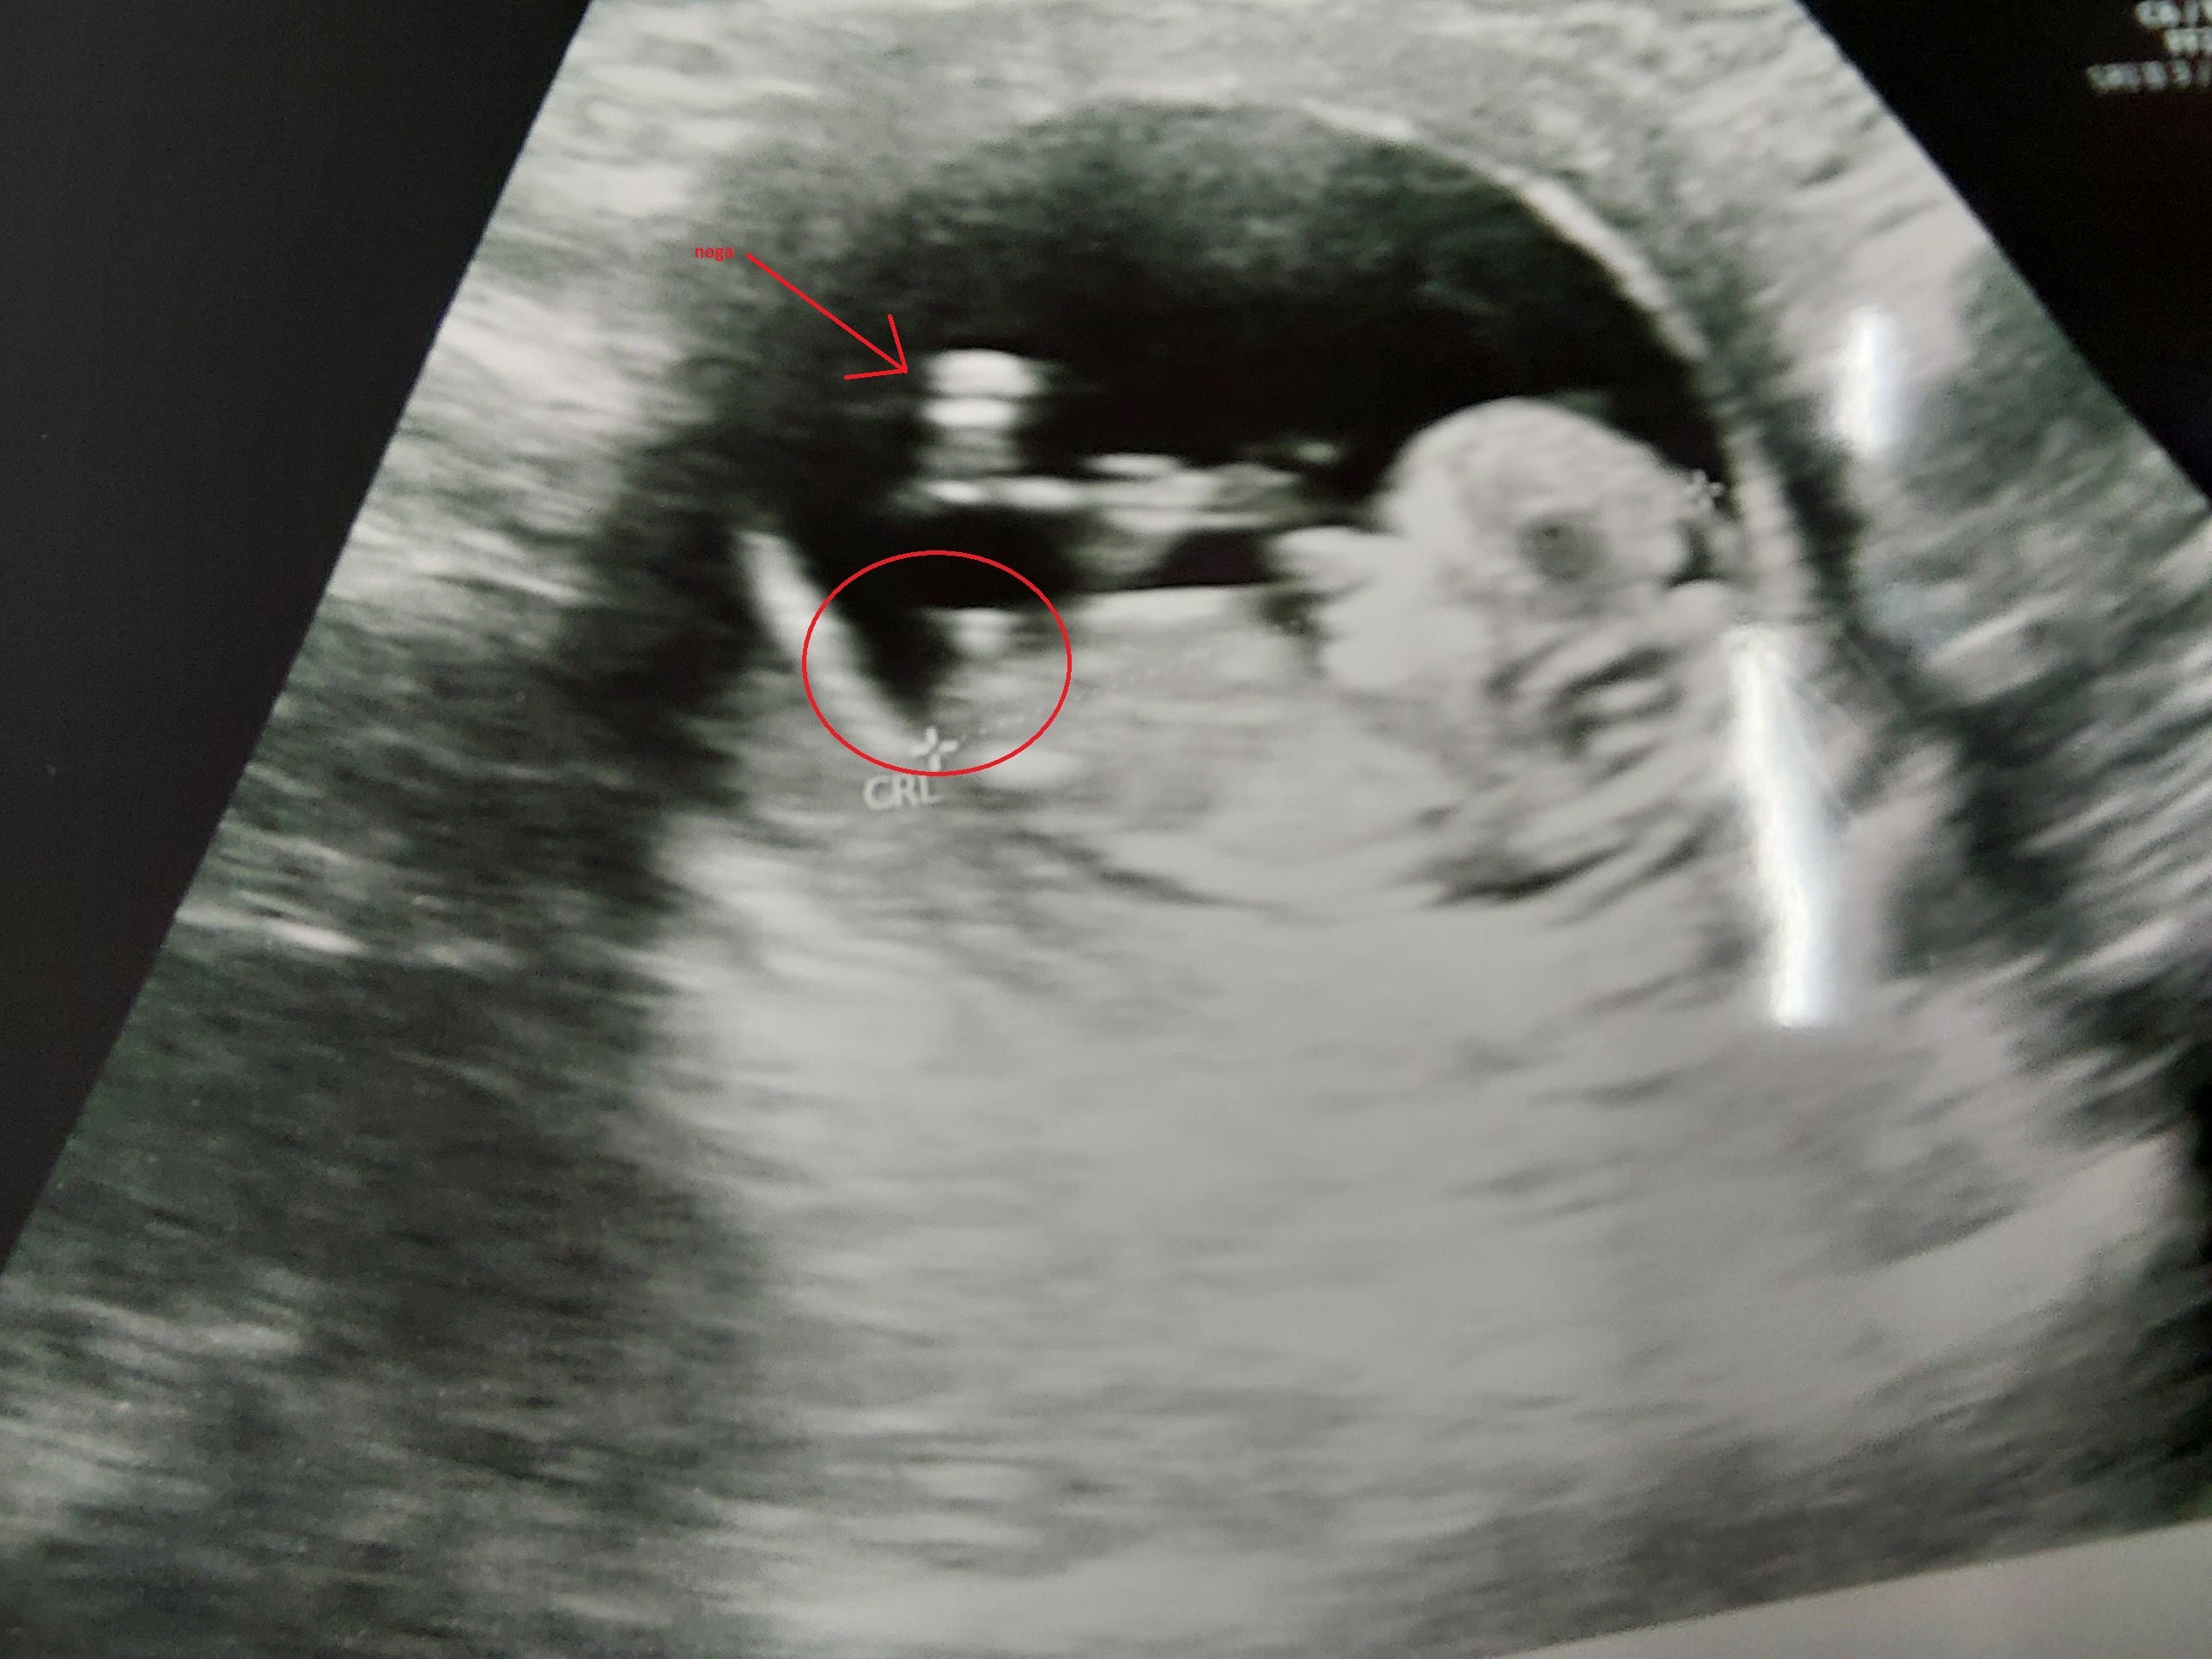

Dla porównania moje zdjęcie z dziś 11+5

Zobacz załącznik 1537851

Ale jeżeli to faktycznie nub to według mnie chłopiec. Za tydzień się okaże![]()